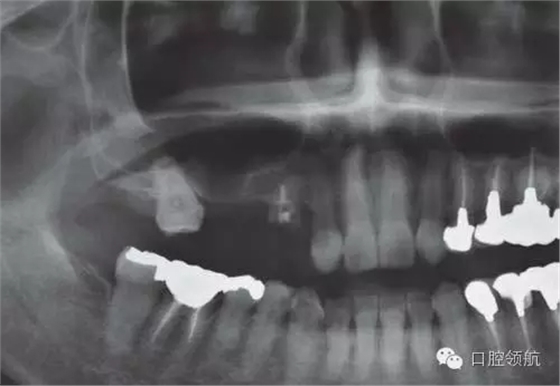

圖1 術前的曲面斷層影像

這個病例,上頜竇底骨量不足,利用內(nèi)提升的方法同期植入。

為了在不足的骨量中獲得良好的初期穩(wěn)定性,種植體沒有埋入過深,所以造成軟組織的不足,雖進行減張切開縫合,但術后仍出現(xiàn)牙齦裂開(圖2~圖5)。